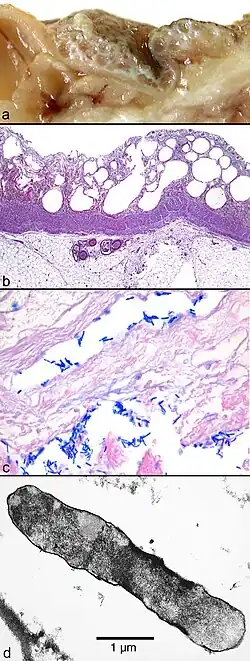

Illustrations

(a) Parois intestinales œdémateuses avec multiples kystes sous-muqueux et sous-séreux. (b) Vue histologique de la muqueuse intestinale avec des nécroses non-réactives. (c) Bactéries (d) Vue en microscopie électronique d'une bactérie trouvée dans un kyste sous-muqueux.